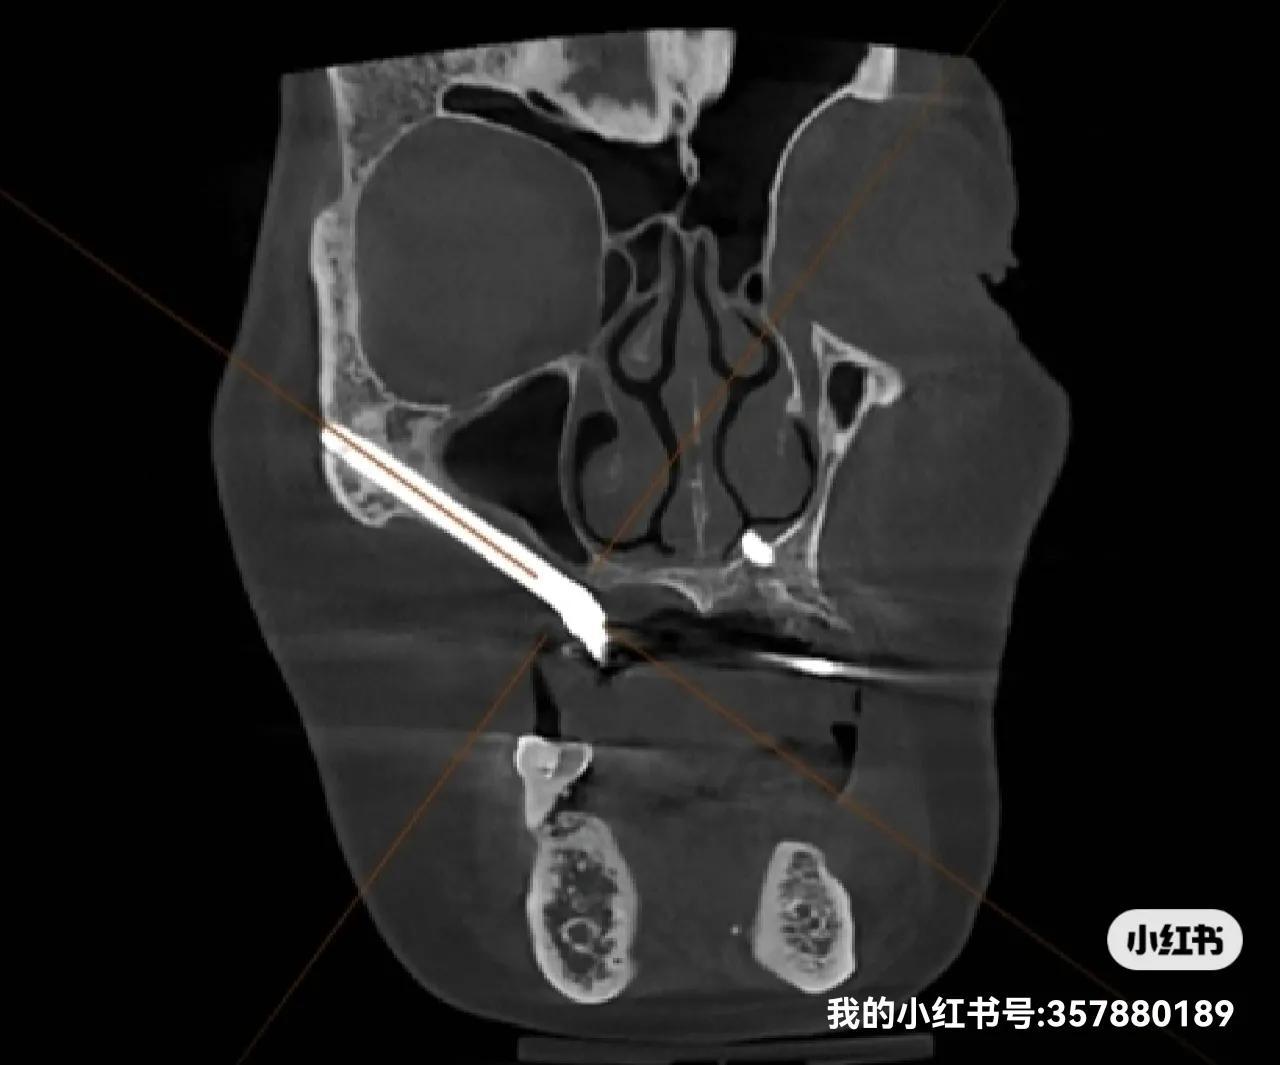

种植牙技术已经迈入了全新的时代,传统的种植牙技术得到了极大的改进和优化,最新的技术包括全数字化种植、3D打印种植导板等,大大提高了种植的精准度和成功率,新的材料和技术使得种植牙的使用寿命更长,更加自然舒适。